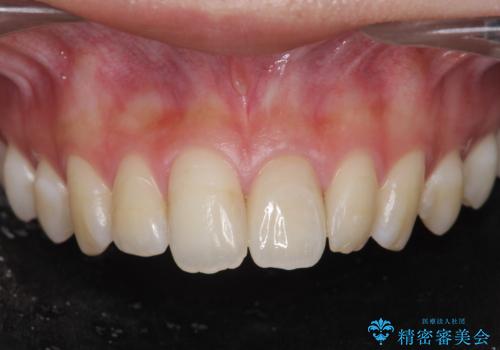

[ 臼歯部インプラント治療 ] 抜けた歯を治療したい

ただ歯のないところにインプラントを入れて、終わり。と言った治療ではなく、長期的に安定した咬合状態を保てるような噛み合わせの整備や清掃しやすいような歯周環境を整えることで良好な治療結果を得ることができました。